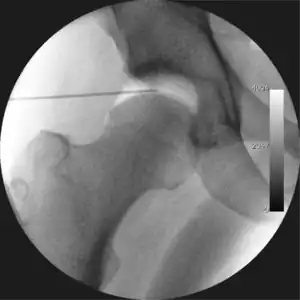

![]() Intraoperative fluoroscopic image during an arthroscopic resection of a cam lesion of the femur. The upper instrument is the arthroscope (viewing device), while the lower is the high-speed burr used for reshaping the bone. |

The procedure is performed with the patient asleep (general anaesthetic) or under spinal anaesthesia. There are two widely used methods, one with the patient on their back (supine) and the other on their side (lateral decubitus). Which is used is down to the surgeon's preference. To gain access to the central compartment of the hip joint (between the ball and socket), traction is applied to the affected leg after placing the foot into a special boot. (See fig. 2) There is specifically designed equipment for this, although some surgeons use a 'traction table', initially designed to help in the operative fixation of broken thigh and lower leg bones. The amount of traction (or pull) needed is assessed with the help of fluoroscopy (low-dose portable x-ray). (See fig. 3) It is usually not possible to distract the ball from the socket with traction alone by more than a few millimetres. Once the surgeon is happy that they will be able to gain access to the hip joint (i.e. the ball will distract from the socket by a small amount), the patient is then painted with antiseptic and the surgical drapes applied.

The next step is to insert a fine needle under x-ray guidance into the hip joint. This breaks the 'suction seal' of the joint and allows further distraction if necessary (see fig 4). The surgeon wishes to see the ball move out the socket by approximately 1 cm, so that access to the hip joint can be achieved with minimal risk of damage to the joint surfaces. Most surgeons will inject fluid into the joint at this stage, again to ensure that there is enough space between the ball and socket for safe instrument access. This needle is then removed. The next step is placement of the 'portals', or the small holes made to pass instruments into the joint. This is achieved by again passing a fresh hollow needle into the joint under x-ray control, usually in a slightly different position. The reason for this is so the surgeon can ensure that the needle, and subsequent cannulae do not penetrate and damage the acetabular labrum or cartilage joint surfaces (see fig. 5). Again, surgeons will have their own preferences as to their preferred placement. Through this hollow needle, a long thin flexible guide wire is passed into the joint, and the needle is removed over it, leaving the guide wire in situ. A small cut in the skin is made around the wire, to allow for larger cannulae to be placed over the wire through the portal. The wire therefore guides the larger cannulae into the joint. The most common external diameters of cannulae used are between 4.5 and 5.5 mm. Once the surgeon is satisfied that the cannula is in the correct position, by a combination of feel and x-ray guidance, the guide wire can be withdrawn. Once the first portal is correctly placed, any further portals may be created once the camera is in position, to ensure that they are placed with minimal risk to the joint surfaces. This process can be repeated to gain as many points of entry to the hip joint as the surgeon requires, normally between two and four. Certain of these entry points will be used for the viewing arthroscope and others for operating instruments.